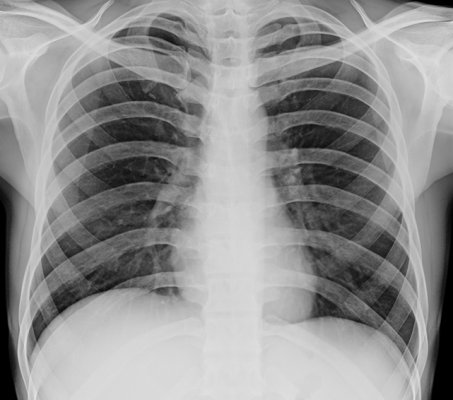

- All types of x-rays can be done at home, and chest x-ray and hip x-rays are commonly done.